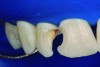

A 12-year-old male presented with extensive carious lesions observed on teeth Nos. 7 through 10, which were accompanied with gingivitis (Figure 1). The pulpal condition was verified through thermal sensitivity tests and vertical percussion, both being satisfactory (Figure 2). The proximity of the lesions with the pulp chamber and the absence of periapical lesions, especially in the right lateral incisor, were observed by the radiographic examination (Figure 3).

Fig 1. Initial aspect showing decayed teeth and gingivitis.

Figure 1